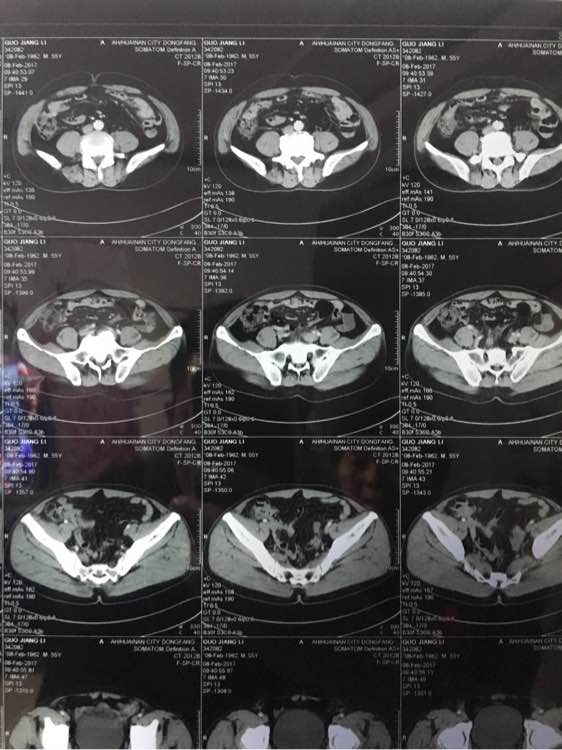

大神看下,几个月前说肠子

ct吧

几个月前说有点东西,肠子上

不懂啊,你看下啥问题

你肚子平常有什么症状?

有病去问医生,哥们,这贴吧里都是普通人,好医生没时间在这扯淡的,找个好点的医生确认,祝你健康!